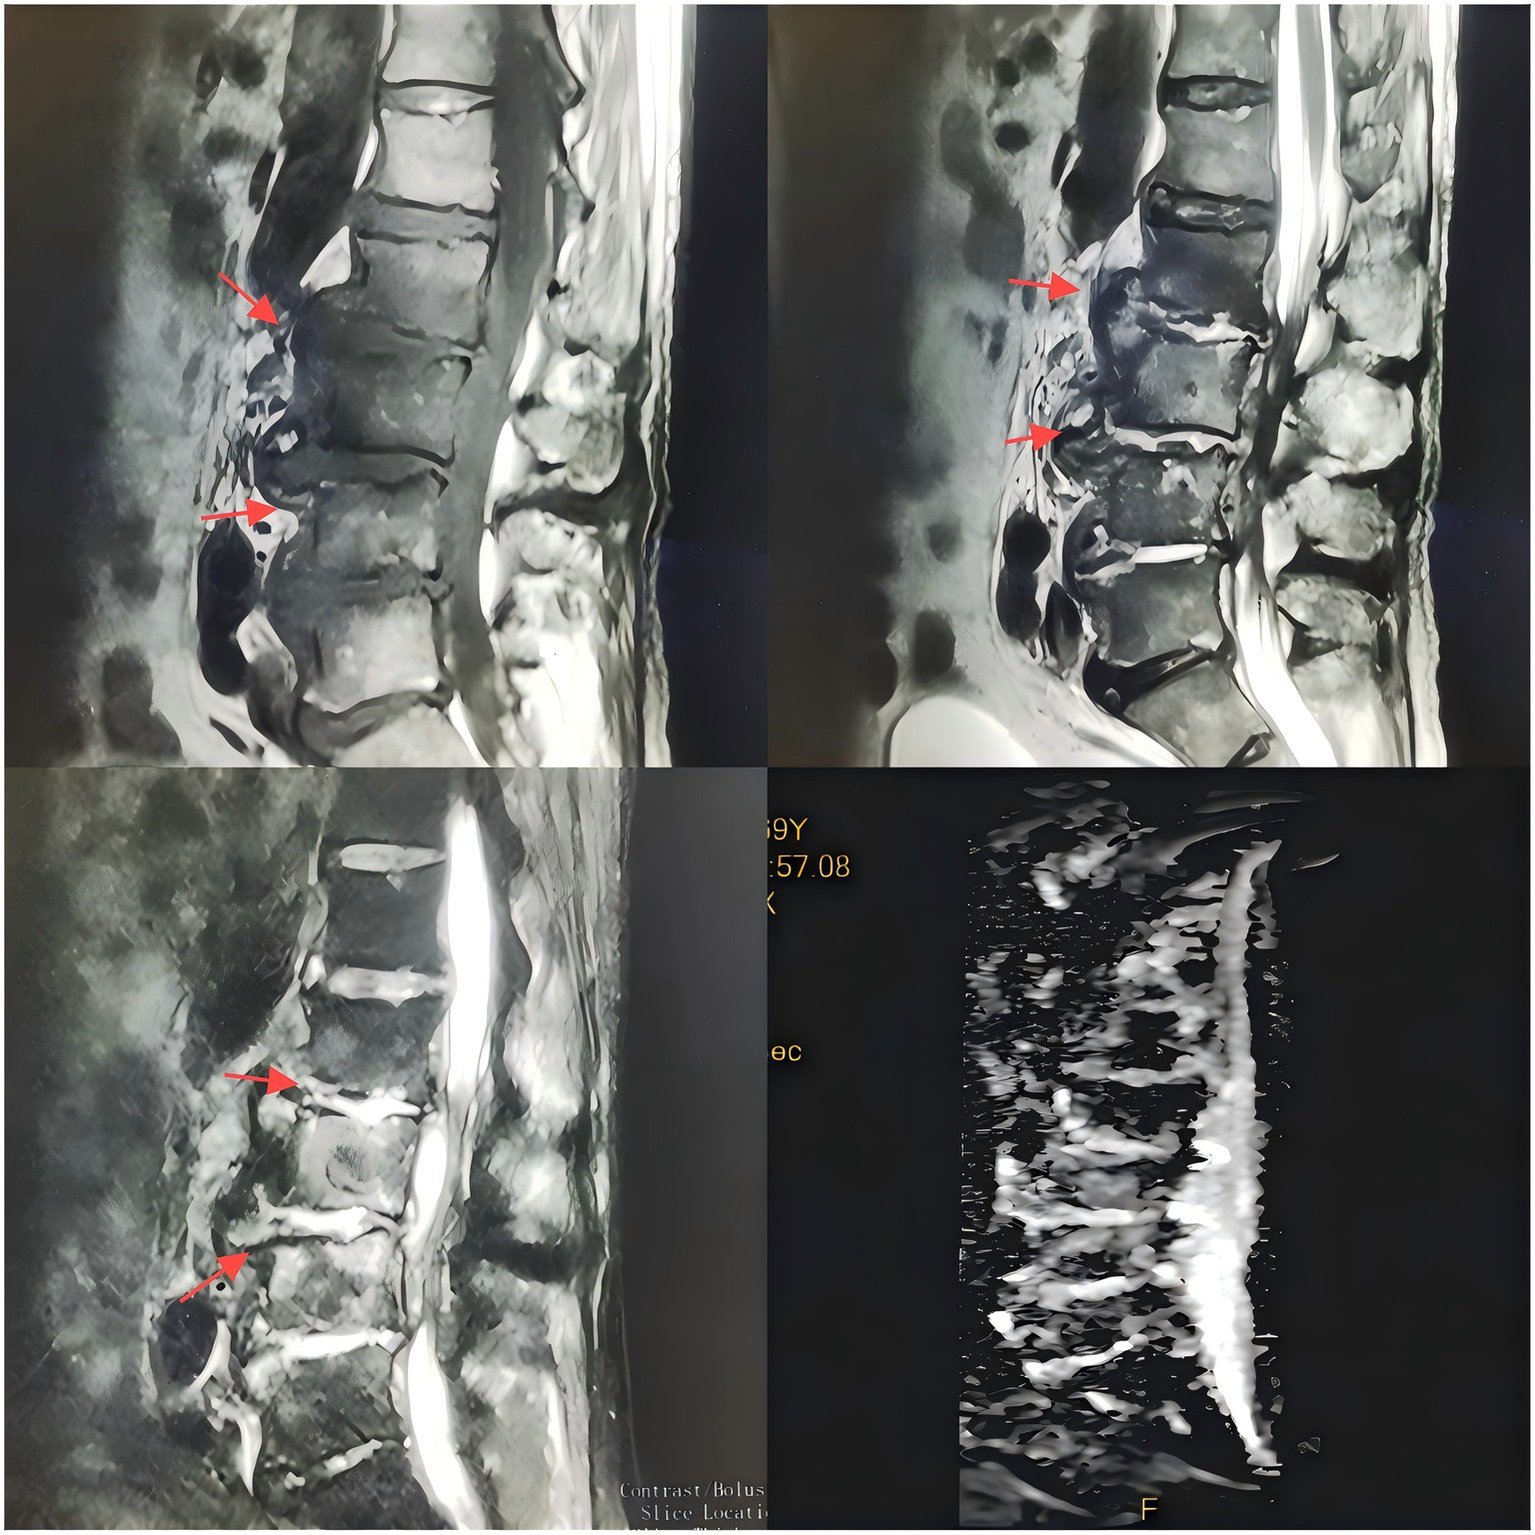

Upon admission, the patient’s body temperature was 40.3 °C, accompanied by chills, fatigue, shortness of breath, and tachycardia, but his blood pressure was normal (126/88 mmHg). Laboratory tests showed a white blood cell count of 8.8 × 109/L (normal range: 3.5–9.5 × 109/L), neutrophil count of 83.10 × 109/L (normal range: 1.8–6.3 × 109/L), lymphocyte count of 11.40 × 109/L (normal range: 1.1–3.2 × 109/L), procalcitonin level of 1.175 ng/mL (normal range: <0.05 ng/mL), interleukin-6 level of 84.46 pg/mL (normal range: <7 pg/mL), erythrocyte sedimentation rate (ESR) of 58 mm/h (normal range: 0–15 mm/h), negative tuberculosis PCR, a negative interferon-gamma release assay (IGRA), negative tuberculosis PCR, negative Brucella agglutination test, negative TORCH test results, and multiple negative blood and sputum cultures. Persistently negative conventional cultures in CREC infections are not uncommon, as these pathogens often require specialized media or prolonged incubation for detection (10). CT scans revealed irregular bone structures in the L2–L5 intervertebral discs, with fluid-filled dark areas around the discs and bilateral psoas muscles, suggesting tuberculous abscess changes. Lumbar MRI showed tuberculosis in the L2–L5 vertebrae, with surrounding soft tissue abscess formation, spinal stenosis at the corresponding segments, and compression of the conus medullaris and cauda equina (Figures 1, 2).

Figure 1

T1-weighted MR images of the intervertebral discs acquired with varying flip angles.